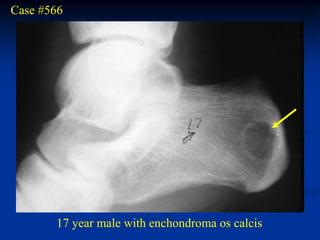

Case #566

17 year male with enchondroma os calcis

Os calcis view